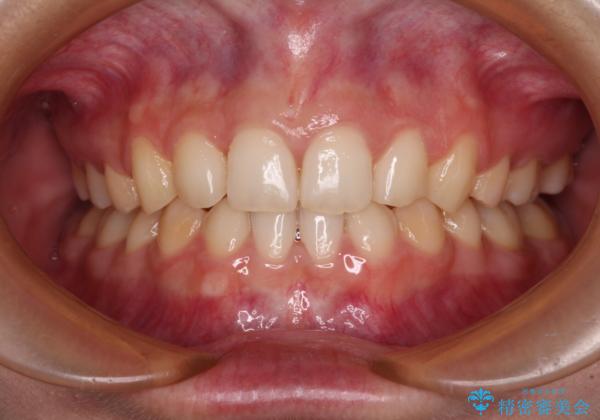

上顎左右第一小臼歯2本を抜歯し、ワイヤー装置にて矯正治療を行うこととしました。

通常の抜歯矯正と抜くべき歯の位置が異なるため、咬みにくさが残ってしまうのではないかと懸念されましたが、咬み合わせに違和感なく、スムーズに治療を終えることができました。